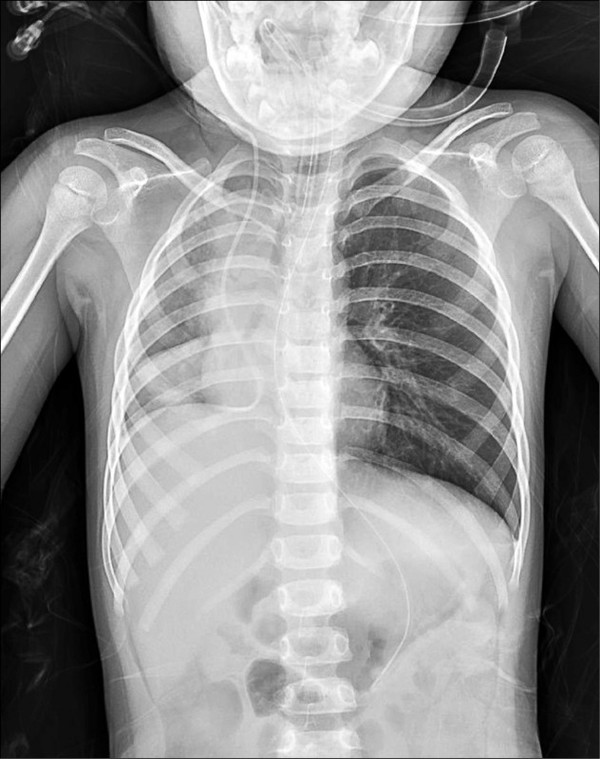

肺腫瘤

16810tn.jpg